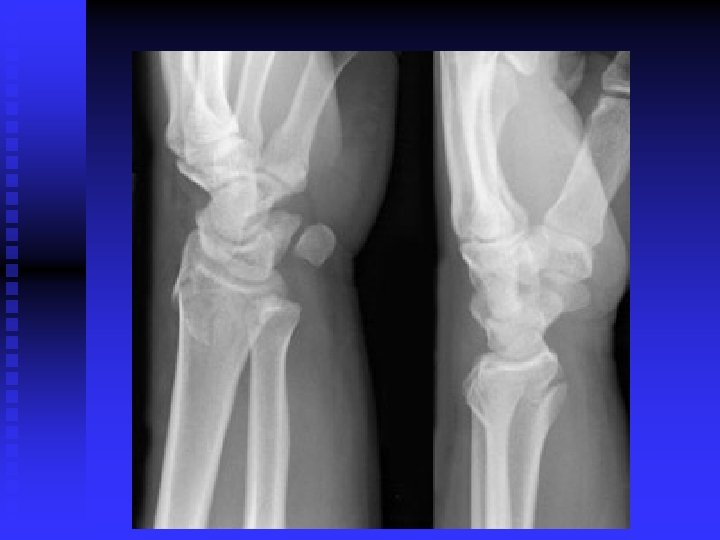

Carpal Tunnel Syndrome n n Median nerve compression within the carpal tunnel is the most common peripheral nerve entrapment syndrome. Any condition that decreases the cross sectional area of the carpal tunnel or increases the volume of its contents may cause the pathology. EX: lunate dislocation; distal radius fracture, sustained flexion or extension postures, fluid retention, synovitis